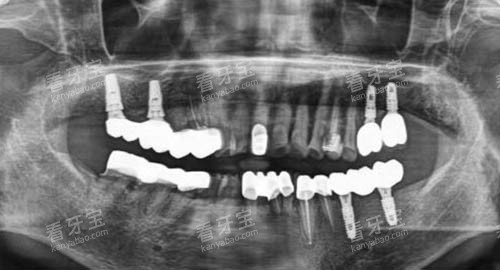

深圳正恩口腔引进了一系列国内外较高的口腔诊疗设备和技术,如智能化口腔全景机、种植导板技术、不痛麻醉技术等。

这些较高的设备和技术为口腔疾病的诊断和治疗提供了更加较准、较高的效率的手段。

例如,智能化口腔全景机可以清晰地显示口腔内部的结构和病变情况,帮助医生做出更较准的诊断;种植导板技术可以提高种植牙的精密度和可行性,减少手术创伤和并发症的发生。